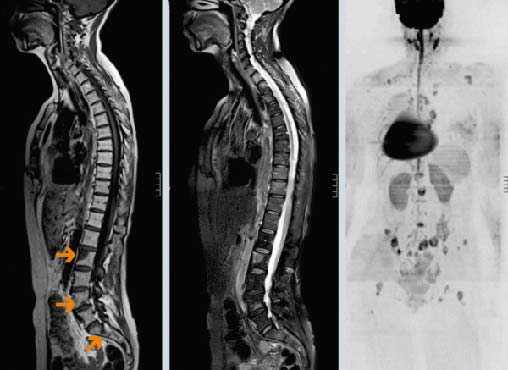

(Слева) Сагиттальный срез, Т1-ВИ с КУ шейного отдела позвоночника: накапливающая контраст высокозлокачественная олигодендроглиома среднего мозга. На уровне спинного мозга видны множественные узелковые и сливающиеся метастазы, сдавливающие спинной мозг

(Справа) На сагиттальном Т1 -ВИ с КУ поясничного отдела позвоночника в просвете спинномозгового канала визуализируются крупные узловидные метастазы, прорастающие между корешками конского хвоста.